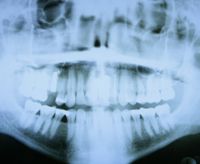

Röntgen ist aus der Zahnmedizin nach wie vor nicht wegzudenken. Mittels Röntgenstrahlen lassen sich äußerlich nicht sichtbare Strukturen, Erkrankungen oder für bestimmte Eingriffe problematische Wurzelverläufe feststellen und entsprechende Behandlungsschritte einleiten. Bei dieser Diagnosetechnik macht man sich die Eigenschaft der Röntgenstrahlen zu Nutze, verschiedene Körperbestandteile und Gewebe unterschiedlich stark zu durchdringen. Die Strahlen treffen anschließend in unterschiedlicher Stärke auf ein belichtungsfähiges Filmmaterial auf und bilden die durchstrahlten Körperregionen ab.

Durch Einzelzahnaufnahmen erstellt der Zahnarzt detaillierte Bilder einzelner Zähne und seiner Nachbarzähne. Das gesamte Gebiss kann zum Beispiel mithilfe des Panoramaröntgengerätes (Orthopantomograph, OPG) aufgenommen werden. Für die Karieserkennung im Zahnzwischenraum bieten sich so genannte Bissflügelaufnahmen an.